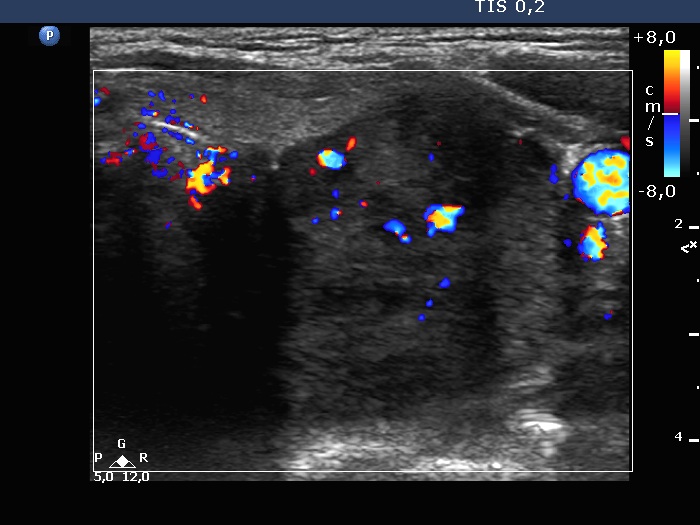

Parathyroid lesions - case 2173 (ultrasonographic picture 5)

Left lobe, transverse view, color Doppler mode. The nodule presents intranodular vascularization.